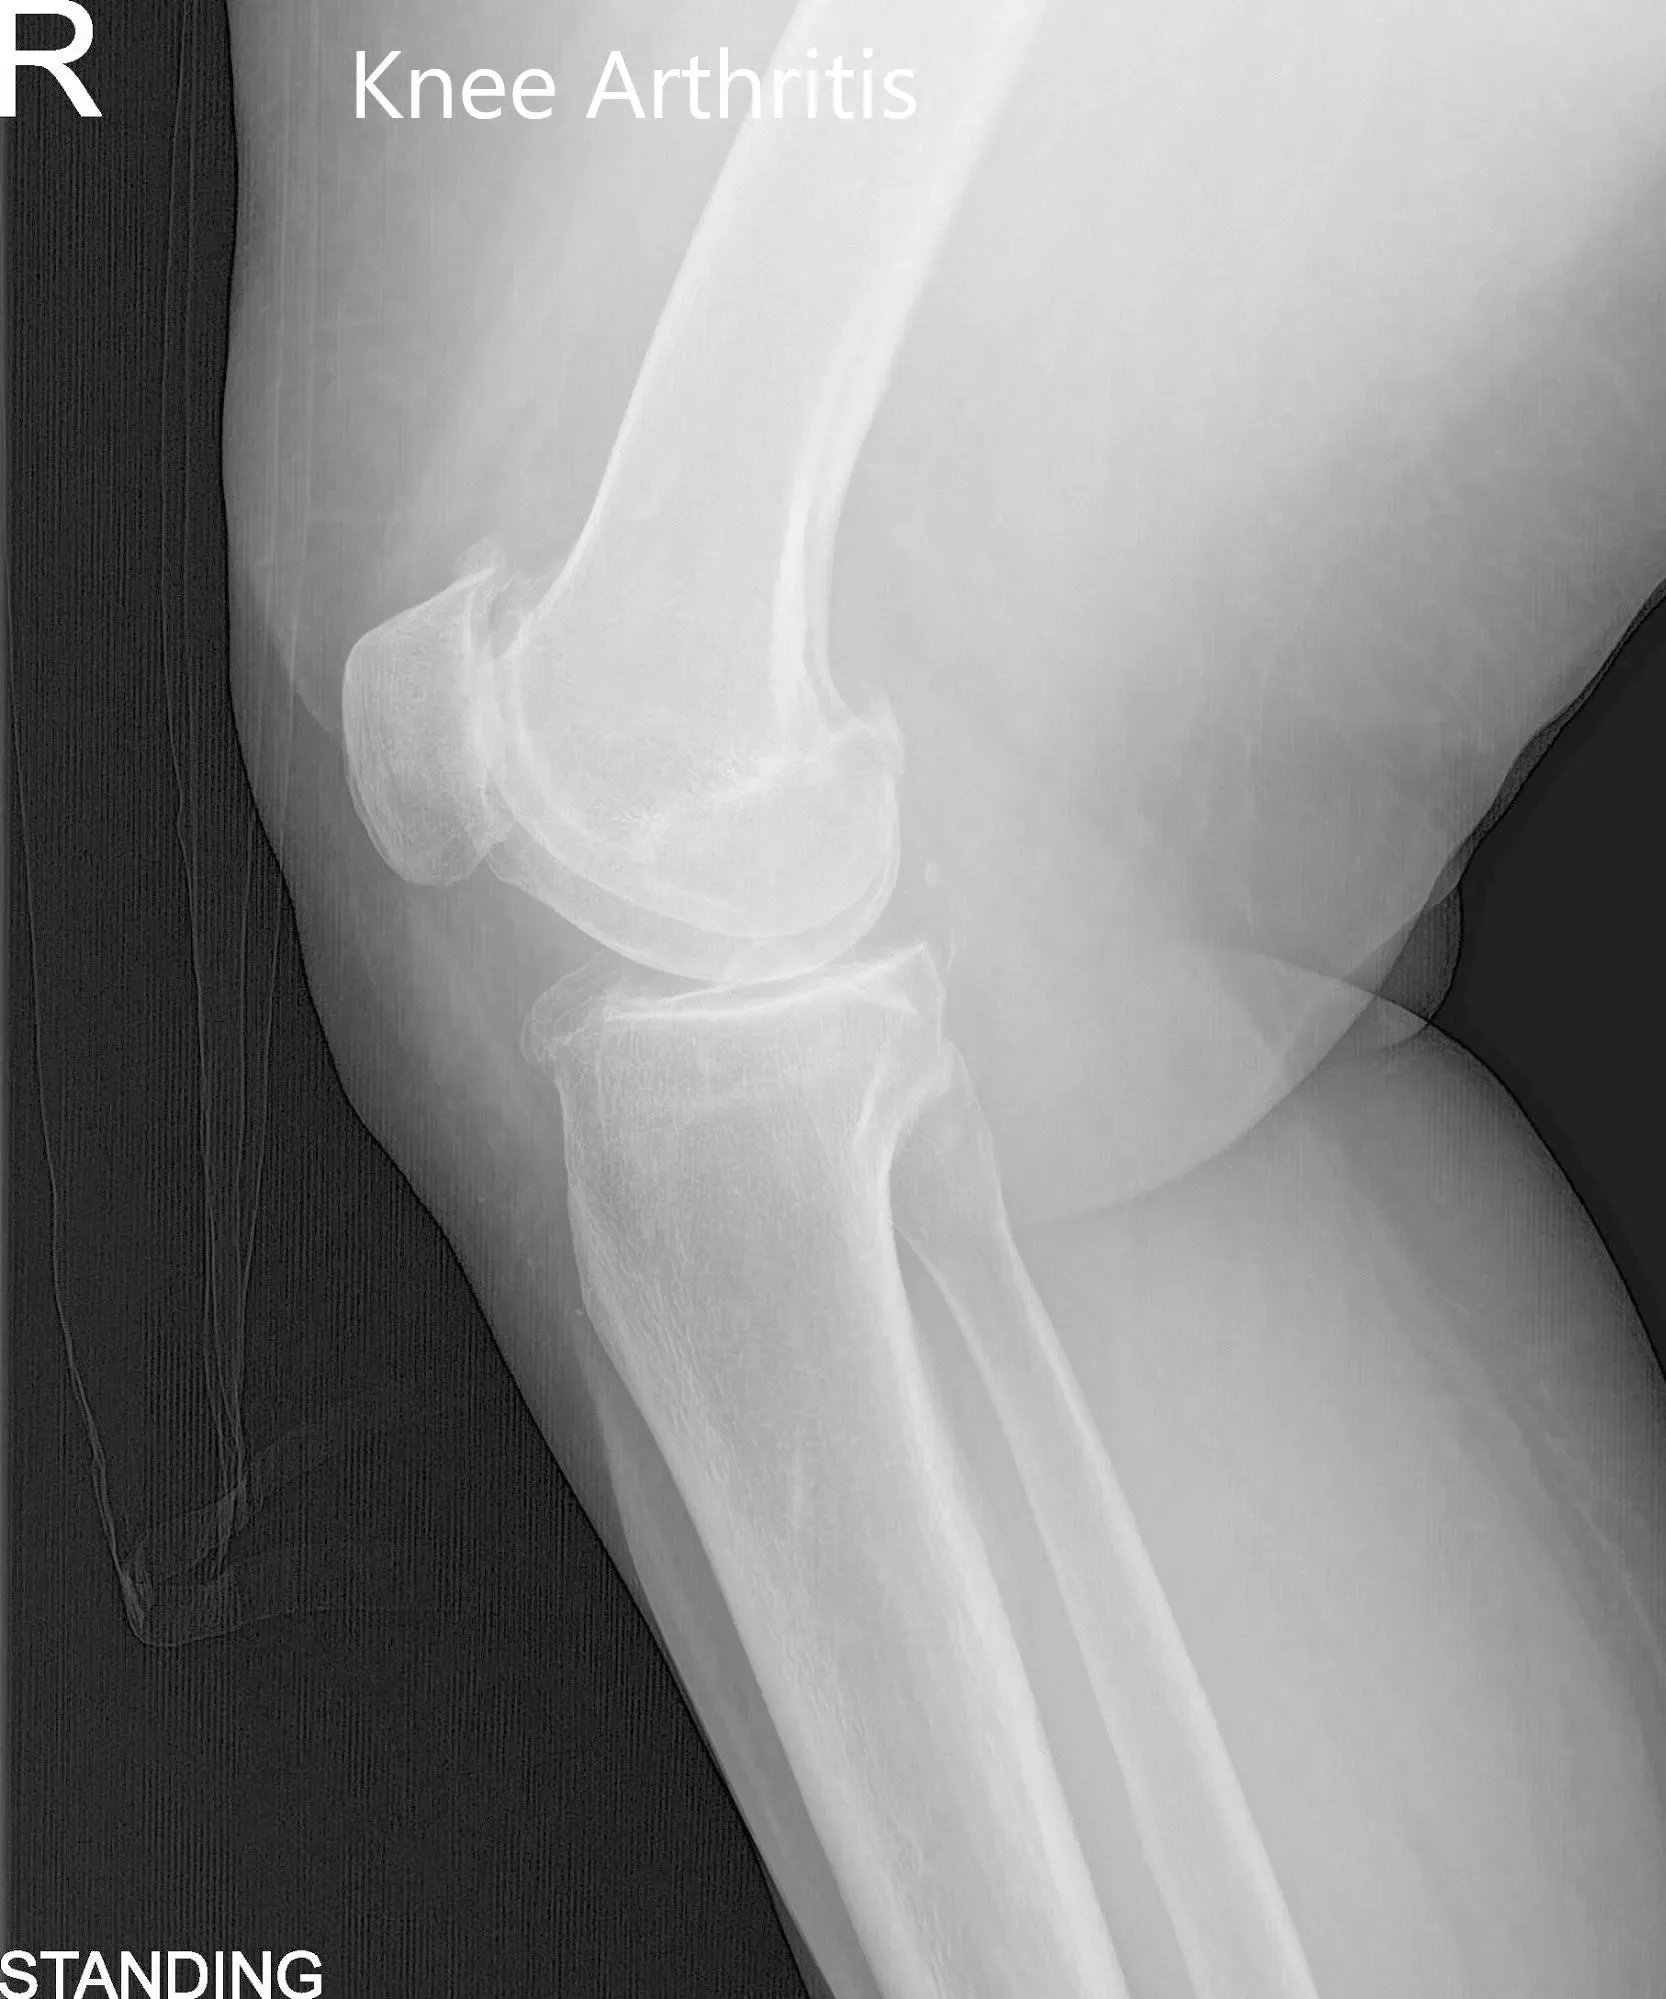

Pre-Operative AP and Lateral X-Ray views of the Right Knee

A 71-year-old female presented to our office with complaints of bilateral knee pain (right greater than left) for the past four years. The patient stated that the pain was getting worse over time despite conservative management in forms of physical therapy, knee injections, and pain medications. The pain severely affected his daily activities such as walking and climbing stairs.

The patient was assessed at the office for surgical management of knee arthritis and was found a suitable candidate for total knee arthroplasty of the right knee. The patient was offered a custom knee replacement system. Risks, benefits, and alternatives were discussed thoroughly, and the patient went ahead for the procedure. The custom knee replacement system includes custom patient-specific implants with custom instrumentation.